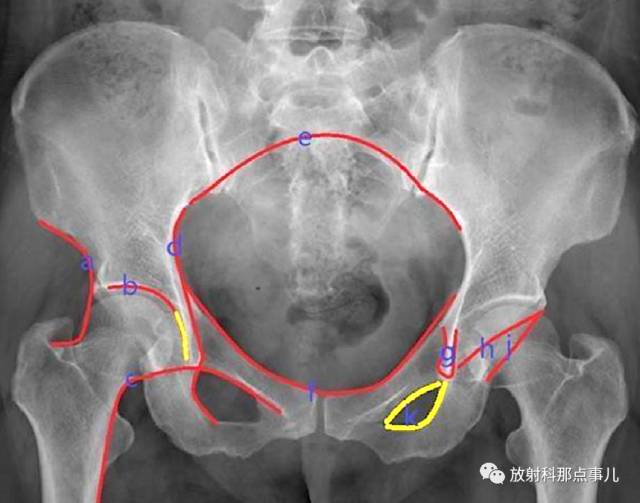

Calve线

卡尔维氏线,即髂颈线。髋关节正位片上,髂前下棘下方髂骨外缘与股骨颈外缘连线所形成的弧线,能够反映股骨头与髋臼的关系及髋臼上缘的完整性。正常为光滑曲线,若不连续提示髋关节脱位或者股骨颈错位骨折。

臼顶线

链接髋臼上缘的弧线,与泪滴外侧缘相延续(黄线),代表髋臼的负重区。

Shenton线

又叫沈通氏线、耻颈线、下弧线,是指成人髋关节正位片上,闭孔上缘与股骨颈内下缘连线,能够反映股骨头与髋臼的关系。正常应为平滑曲线,若不连续提示髋关节脱位或者股骨颈错位骨折。

Kohler线

即髂坐线,髂骨内缘切线与坐骨体内缘的连线,正常时为连续光滑曲线,髋臼陷入症时髋臼突至此线内侧。

髂骶线

连接髂骨弓状线与骶骨岬的弧线,代表骨盆后环的完整性。

髂耻线

连接双侧髂骨內缘与耻骨上缘的弧线,代表骨盆前环的完整性。

泪滴线(U形线)

连接泪滴周围所形成的曲线,代表髋臼的內缘,一般用于髋臼假体深度的评价,髋臼內缘紧邻泪滴线的外缘。

前唇线

髋臼前缘所连成的弧线,代编髋臼前壁的完整性。

后唇线

髂骨外缘与髋臼后缘所连成的弧线,代表髋臼后壁的完整性。

闭孔内缘线

沿闭孔內缘所连成的弧线,正常情况下双侧闭孔对称,当骨盆旋转时可发生改变。